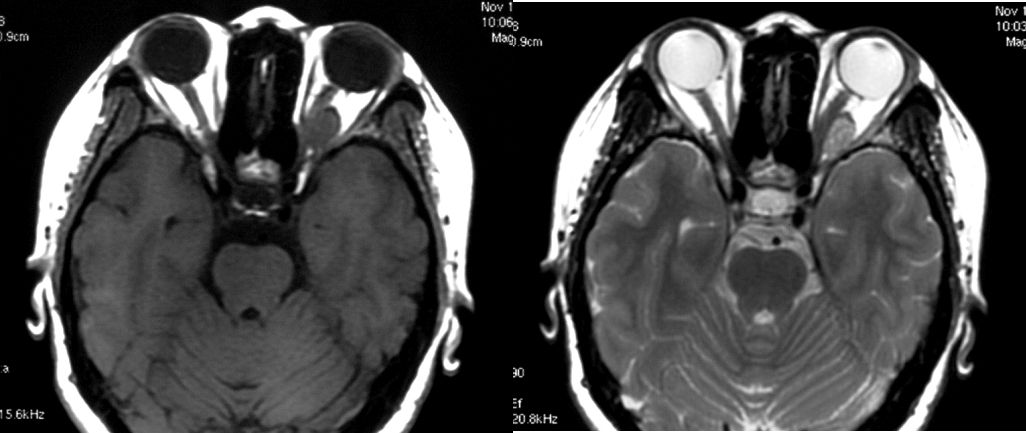

患者女,35岁,左眶海绵状血管瘤,患者主因左侧偏头痛5年,左眼突出2个月,于2007-1-17行伽玛刀治疗:病灶容积6.4ml。GKS后6个月时突眼症状缓解,10个月时复查MRI肿瘤明显缩小。

A 伽玛刀定位MRI T1WI B伽玛刀定位MRI T2WI

C 伽玛刀治疗后10个月MRI T1WI D 伽玛刀治疗后10个月MRI T2WI